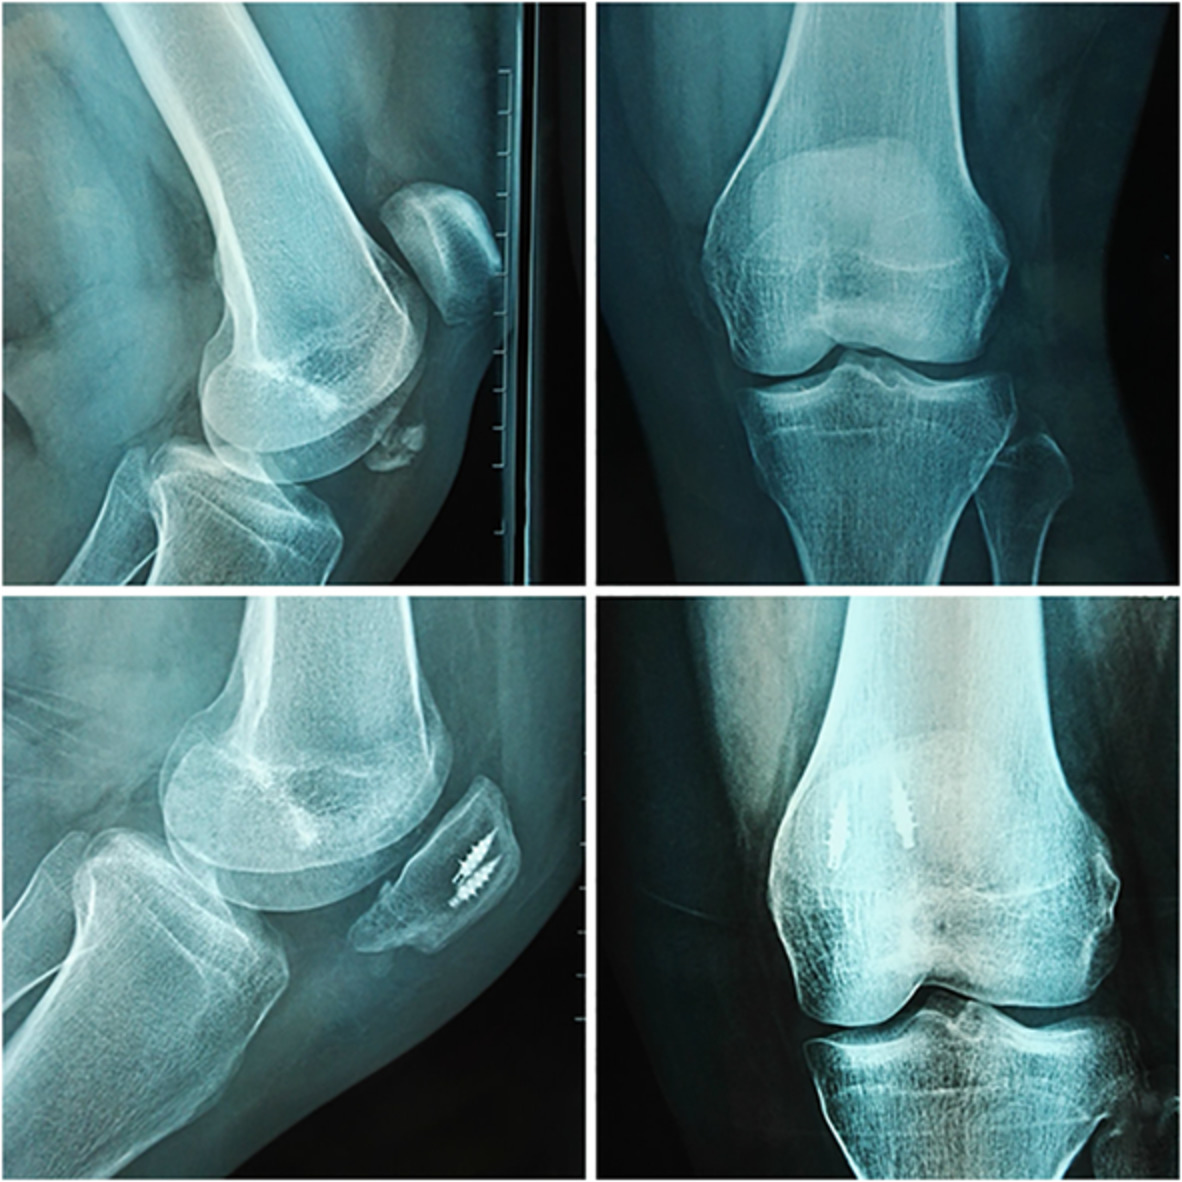

TABLE 2. Postoperative complications according to surgical technique Technique n Infection n (%) Nonunion n (%) Implant failure n (%) Reoperation sn (%) AS 10 1 (10%) 0 0 0 K-wire 18 2 (11.1%) 2 (11.1%) 3 (16.7%) 3 (16.7%) Total 28 3 (10.7%) 2 (7.1%) 3 (10.7%) 3 (10.7%) AS, Anchor and Krackow-“8” suture fixation; K-wire, Kirschner wire. image

Anterioposterior and lateral knee radiographs of a 65-year-old female patient. (A,B) Patients with distal pole patellar fractures; (C,D) after treatment with anchor and Krackow-“8” suture fixation.

image

Anterioposterior and lateral knee radiographs of a 52-year-old male patient (A,B) Patients with distal pole patellar fractures; (C,D) after treatment with anchor and Krackow-“8” suture fixation.

Anterioposterior and lateral knee radiographs of a 55-year-old male patient (A,B) Patients with distal pole patellar fractures; (C,D) after treatment with anchor and Krackow-“8” suture fixation.